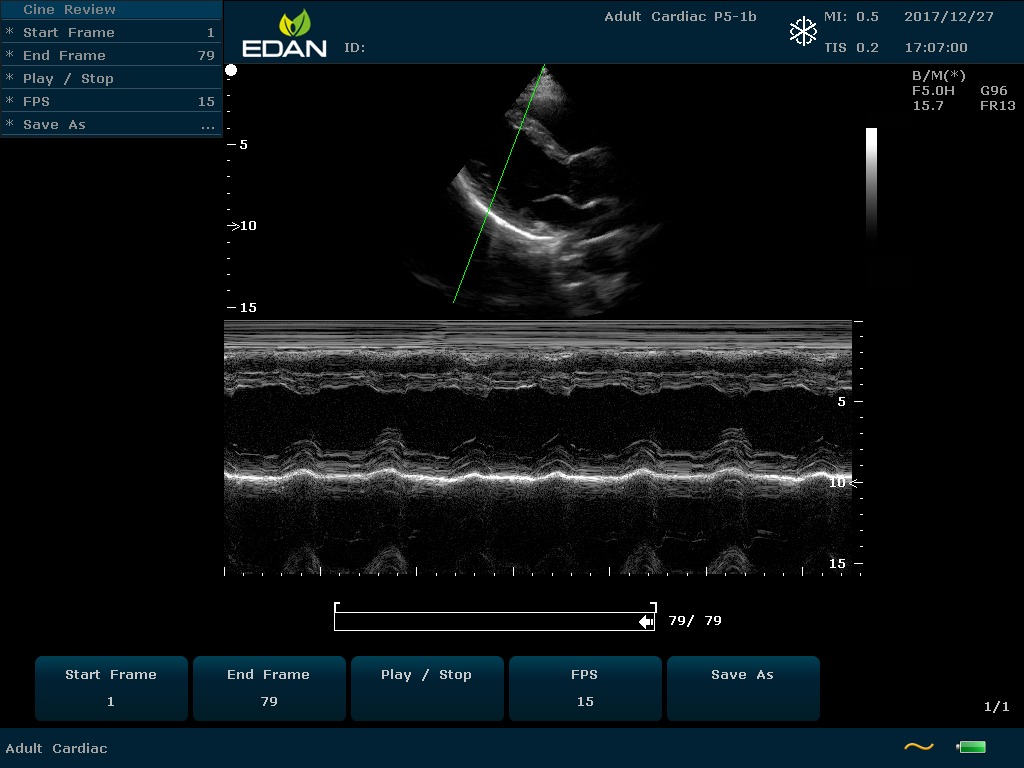

Особенность U60 Edan — расширенное применение. Ультразвуковой аппарат рекомендован для абдоминальных исследований, гинекологии и акушерства, кардиологии, педиатрии, урологии, изучения малых органов, сосудов. Для U60 Edan используются конвексные, линейные, фазированные и внутриполостные датчики.

Передовые технологии позволяют повысить качество визуализации в несколько раз. УЗИ-аппарат U60 Edan отличается возможностью быстрой настройки визуализации. Специальные функции позволяют моментально отображать данные за счет быстрой оптимизации параметров. Режимы визуализации: B-mode, M-mode, Color Doppler, Power Doppler Imaging, Pulsed Wave Doppler, Continuous Doppler.